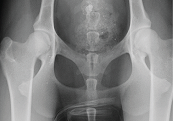

Fig 1: X-ray showing normal hips

Examination may reveal muscle wastage (atrophy), especially over the hips. Manipulation of the hip joints may cause pain and instability may be visible. X-rays are necessary to diagnose hip dysplasia, allowing the severity of the abnormal joint development and presence of secondary osteoarthritis to be assessed.